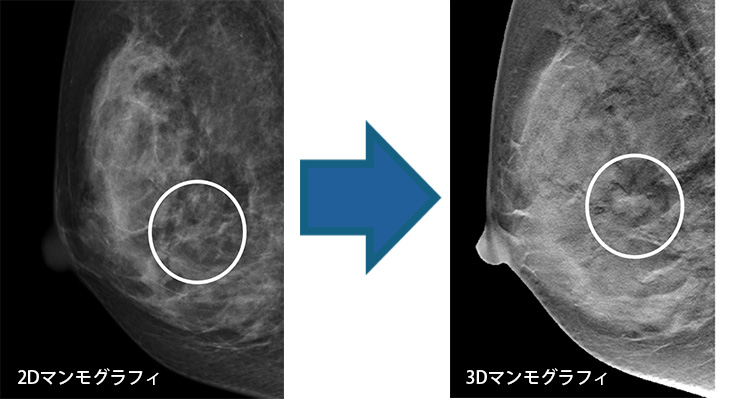

3Dマンモグラフィ(トモシンセシス)

新しい機能である乳房トモシンセシスが搭載されています。

従来のマンモグラフィではできなかった多方向からの撮影が可能となりました。乳腺内に隠れて見えなかった病変が確認できるようになります。